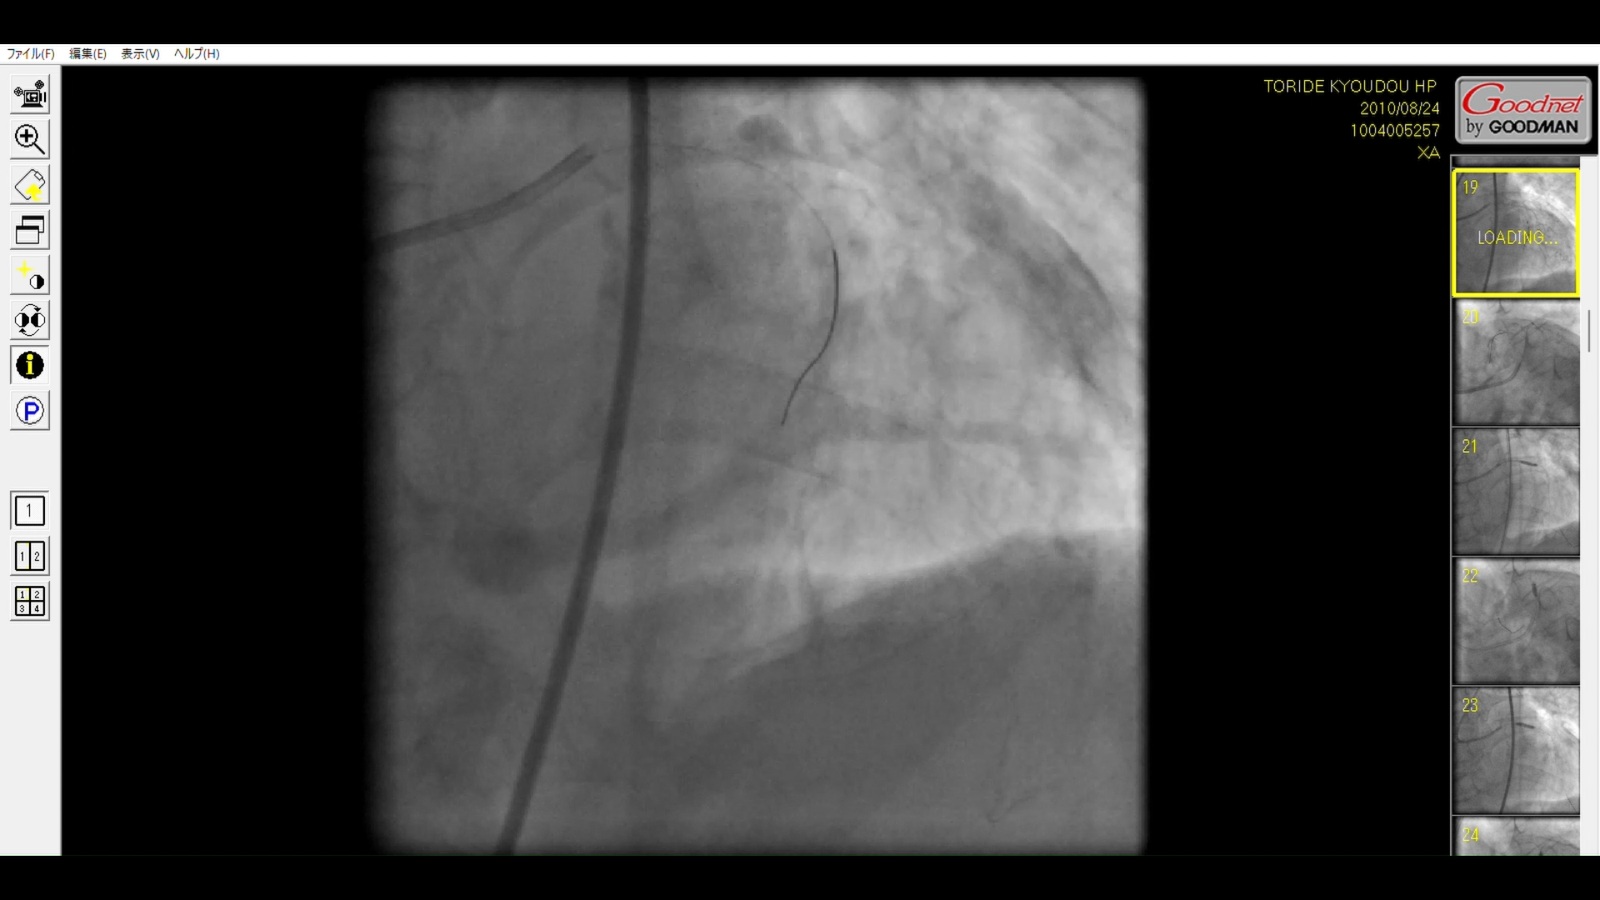

Caption: Evidence of Type III Coronary Perforation

Medical Findings:

Guidewire Deviation: The distal tip of the guidewire is clearly visible outside the anatomical boundaries of the LAD lumen.

Contrast Extravasation: Significant pooling of contrast media ("Staining") is observed in the pericardial space.

Significance: This is a catastrophic complication leading to rapid Cardiac Tamponade. The footage confirms a direct vascular injury that would require immediate surgical intervention or pericardiocentesis.